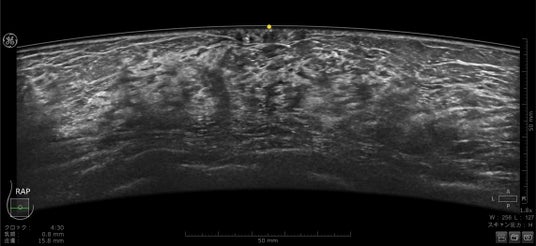

Invenia ABUS Premium で収集された乳房画像(乳頭直下「図黄色点」が描出されている)

乳房にあてるプローブは、よりフィットするように設計され、周波数帯域も広がったことで空間分解能とコントラスト分解能が向上しています。全ピクセルにフォーカスがあたる信号処理、乳頭直下が見えやすくなる画像処理は刷新され、より均一性の高い画像を提供します。